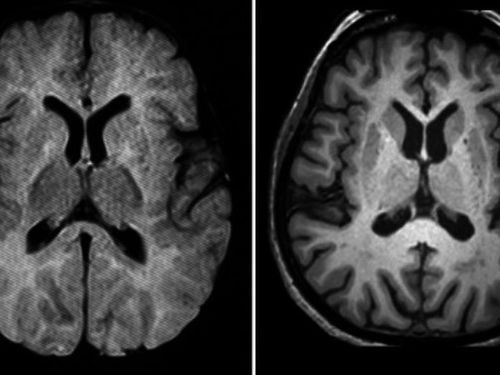

Un nuevo fármaco consigue frenar por primera vez la enfermedad de Huntington

El medicamento, desarrollado por un grupo de investigadores británicos, ha logrado reducir el nivel de la proteína tóxica que causa este grave trastorno neurodegenerativo.